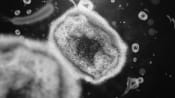

FILE - This undated image provided by the National Institute of Allergy and Infectious Diseases shows a colorized transmission electron micrograph of monkeypox particles (red) found within an infected cell (blue), cultured in the laboratory that was captured and color-enhanced at the NIAID Integrated Research Facility in Fort Detrick, Md. (NIAID via AP, File)